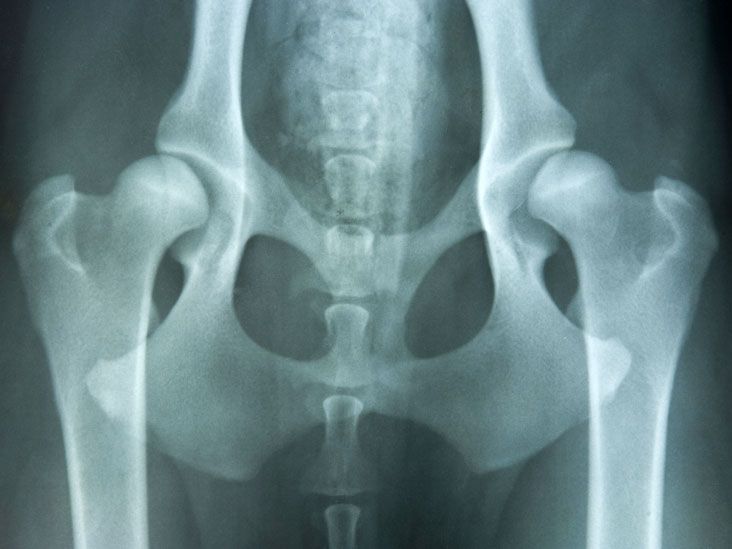

Developmental Dysplasia of the Hip (DDH) is one of the most common pediatric orthopedic conditions. Early diagnosis is crucial, as timely treatment helps prevent long-term complications such as gait abnormalities and early osteoarthritis. A structured approach to assessment and rehabilitation is essential for optimal outcomes.

The condition is formerly known as congenital dislocation of the hip. It comprises a spectrum of disorders: acetabular dysplasia without displacement, instability, and feratological forms of malarticulation.

The reported incidence of neonatal hip instability is 5-20 per 1000 live births; most of the hips stabilize spontaneously, and the incidence of re-stabilization is only 1 or 2 per 1000 infants. Girls are much more affected than boys, the ratio being about 7:1. The left hip is often affected than the right; in 1 in 5 cases, the condition is bilateral.